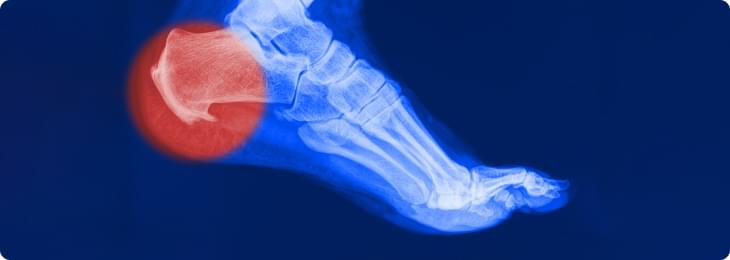

Подошвенной фасцией называют жесткую сухожильную пластинку, которая прикрепляется к пяточной кости и головкам плюсневых костей, создавая своеобразный защитный чехол для подошвенной поверхности стопы. Она помогает поддержанию формы ступни и свода стопы. Нормальная анатомия стопы устроена так, чтобы человек при ходьбе не ощущал боли - для этого имеется подошвенный апоневроз, который играет роль амортизатора (мостика) для свода стопы. Подошвенная фасция натянута как тетива между костями и при каждом шаге эта своеобразная тетива натягивается, удерживая свод стопы, не давая костям стопы «разъехаться».

К сожалению, избыточный вес, повышенные физические нагрузки, высокие каблуки или тесная модельная обувь, плоскостопие приводят к тому, что подошвенная фасция в процессе ходьбы перерастягивает и травмируется, возникают микроповреждения волокон, воспаление.

Воспаление приводит к образованию отека, прорастанию микрососудов и мелких нервных веточек в поврежденную фасцию, возникает боль. Особенно сильно боль проявляется после ночного сна и покоя, так называемая «стартовая боль». Оставшиеся неповрежденными волокна подошвенной фасции начинают работать вместо разорванных, испытывая повышенную нагрузку, и тоже повреждаются. Воспаление и боль прогрессируют, заставляя снизить нагрузку.